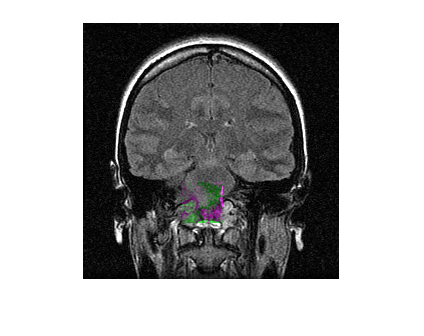

Load a MAT file containing a reference volume into the workspace. Convert the reference volume to data type double.

load mristack.mat

fixed = im2double(squeeze(mristack));Create a deformed volume using local transformations.

local = fixed(160:200,100:140,:); local = imrotate(local,90); moving = fixed; moving(160:200,100:140,:) = local;

Display a slice of the fixed volume and a corresponding slice of the moving volume. Observe the deformation in the alignment of the volumes.

figure imshowpair(fixed(:,:,10),moving(:,:,10))

Register the moving volume to the fixed volume.

[dispField,reg]=imregdeform(moving,fixed,GridRegularization=0.001);

Display the same slice of the fixed volume and the corresponding slice of the registered volume. Observe the improved alignment of the volumes.

figure imshowpair(fixed(:,:,10),reg(:,:,10))